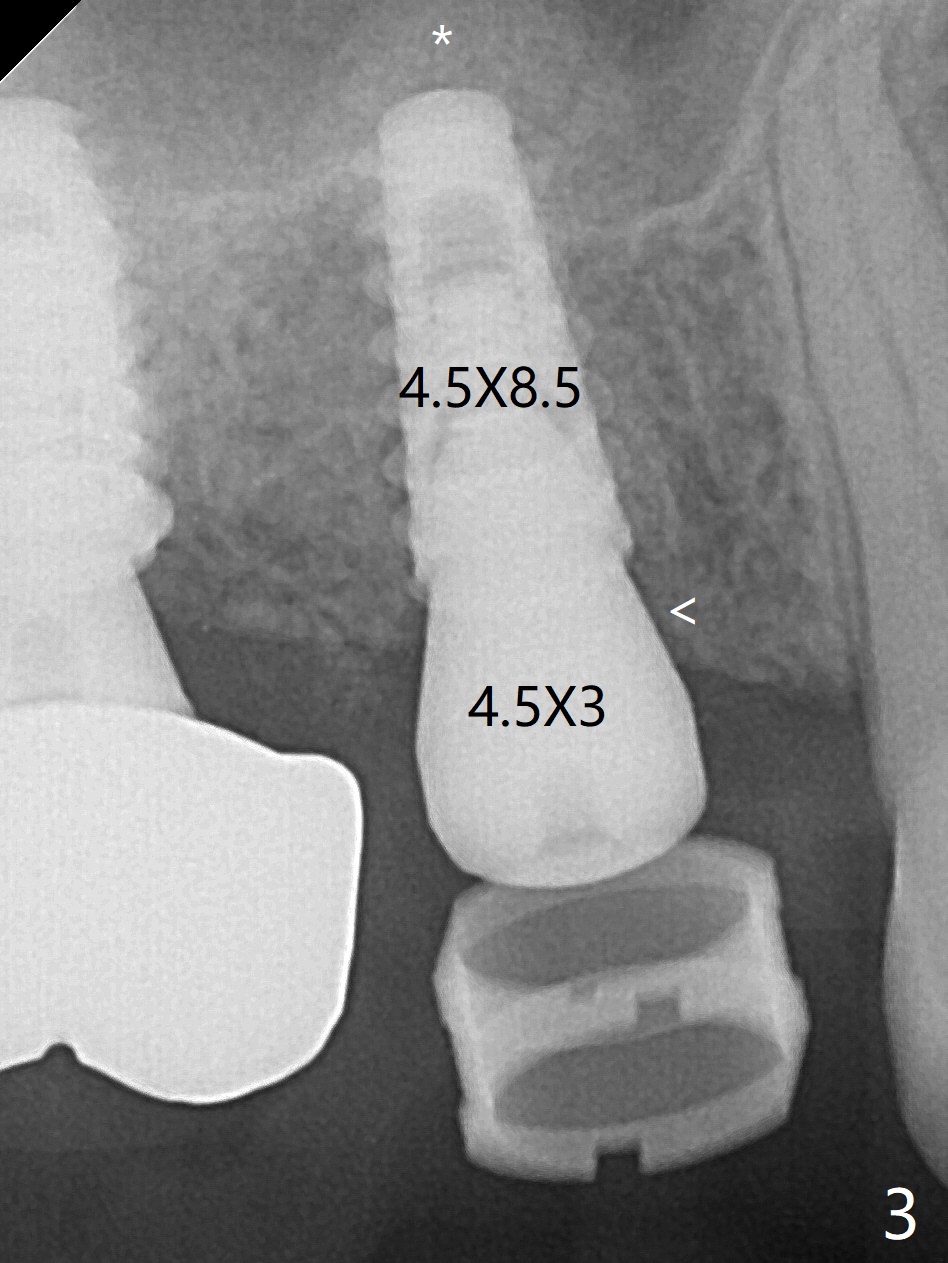

58岁男3号牙位点保存后11个月回来种植,在导板指引下,完成钻洞(3.5x7.3毫米钻头),窦底好像没有破裂,但是仍放置粘性骨粉,使用4x8.5毫米报废植体提升,没有成功。使用2.2x8.5和3.0x8.5毫米钻头,加放骨粉,再次旋入报废植体(大约7.3毫米,图一),骨粉进入上颌窦(*)。使用3.5x8.5毫米钻头后,放置骨粉,植入正式4.5x9毫米(图二,~15Ncm),由于骨扩张,临床检查也证明腭侧(P)不需要植骨,植体周围骨质密度增加。使用5.5毫米Profile钻头(图三:<)后,放置4.5x3毫米愈合基台,PRF膜插入后者和牙龈之间。